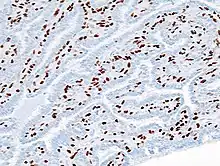

| Histopathology of intraductal papilloma of the breast by excisional biopsy. Immunostaining for p63 protein. | |

_p63.JPG.webp)